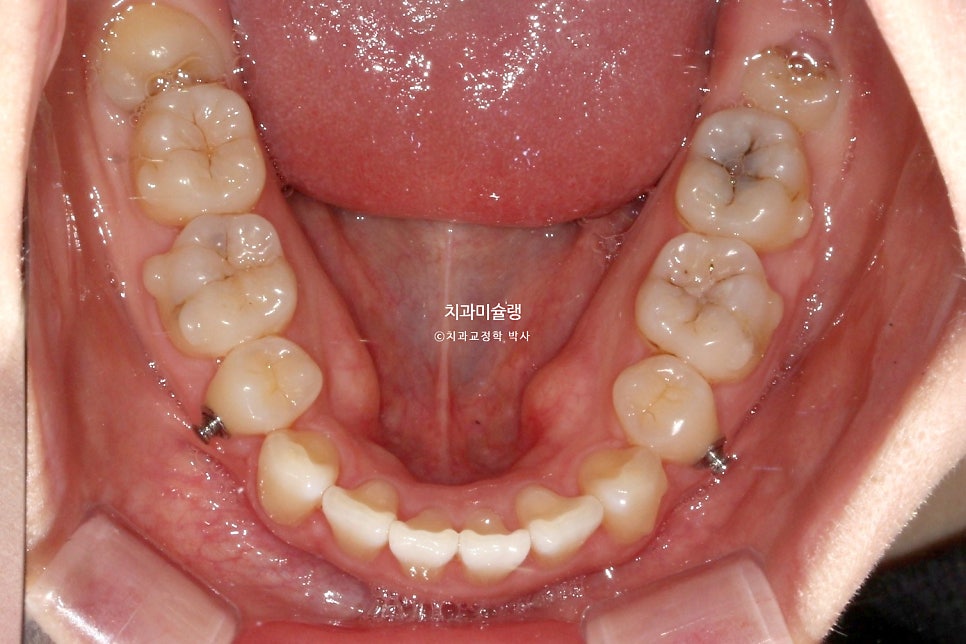

5주간 마지막 세트의 추가장치를 더 낀후 드디어 치료를 마무리 합니다.

총 치료기간은 3년 2개월, 재제작은 3회 했습니다.

본원에서 인비절라인 발치교정 환자분들의 평균 치료 기간은 2년6개월 정도이니, 치료를 길게한 편입니다.

재제작을 3회 했으니 중간에 장치제작기간 기다린 시간을 빼면 실제 치료기간은 2년 8개월쯤 됩니다.

어금니 교합은 물샐틈 없는 1급 교합관계를 보입니다.

발치공간은 깔끔히 마무리 되었습니다.

환자분이 가장 고치고 싶어했던 앞니각도는 깔끔해졌습니다.